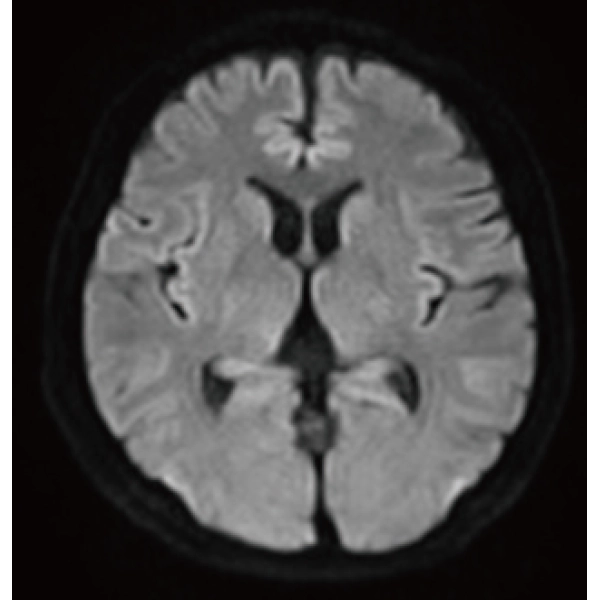

Deep Learning technology*8 enables image quality adjustment after imaging is complete. It optimize SNR and improve image sharpness by processing MRI signals in stages (k-space signal processing). This brings super-resolution and reduces truncation artifacts.

"DLR" is applicable to all body parts and promotes high speed imaging and diagnostic efficiency

IP-RAPID x DLR Plus can also shorten imaging time, allowing more images to be taken in the same examination time.